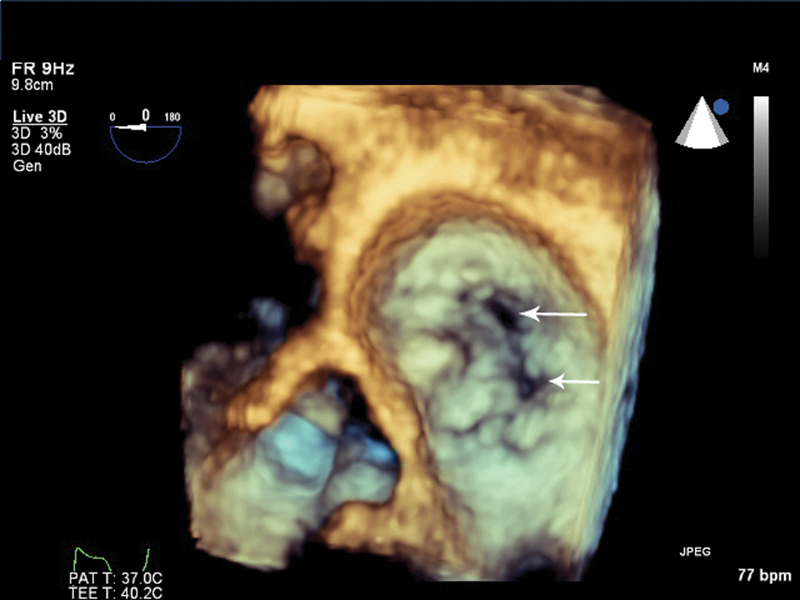

فحوصات تشخيصية لبعض امراض القلب والشرايين التاجية